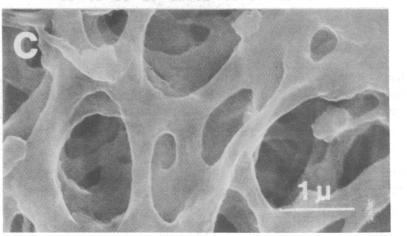

We covalently linked to regenerated cellulose filters a high-affinity monoclonal IgM produced against epitopes that reside on hepatitis B viral surface antigen (HBsAg). Conditions were established whereby as much as 250 micrograms of anti-HBsAg IgM could be linked to 2-4 mg of regenerated cellulose acetate by using cyanogen bromide and trichloro-s-triazine coupling agents. The immunoreactivity of the monoclonal anti-HBsAg IgM was preserved, and quantitative binding studies with HBsAg suggests that more than one functional binding site on the IgM molecule was operative. The specificity of the monoclonal anti-HBsAg IgM was established by demonstrating that a nonspecific monoclonal IgM (against influenza hemagglutinin), when coupled to the filters under identical conditions, had no effect on removal of HBsAg from serum. Most importantly, the monoclonal anti-HBsAg IgM-coupled filters quantitatively removed low levels of HBsAg from serum; after the third pass through the filter, HBsAg was undetectable in the perfusate. Further, the stability of the covalent bond between the anti-HBsAg IgM and regenerated cellulose acetate was shown by the lack of detectable murine monoclonal anti-HBsAg IgM in filtered serum despite 50 passages through the filter. Thus, we have demonstrated that monoclonal IgM antibodies with predefined specificity, when coupled to a biocompatible solid-phase support, may serve as a high-affinity and specific immunoabsorbant for quantitative removal and recovery of viral antigens from human serum. By using this approach, specific removal and recovery of many other substances from serum or plasma would seem possible.

我们将针对乙型肝炎病毒表面抗原(HBsAg)表位产生的高亲和力单克隆IgM共价连接到再生纤维素滤膜上。通过使用溴化氰和三氯-s-三嗪偶联剂,建立了条件,使得多达250微克的抗HBsAg IgM能够与2 - 4毫克的再生醋酸纤维素相连。单克隆抗HBsAg IgM的免疫反应性得以保留,并且与HBsAg的定量结合研究表明IgM分子上不止一个功能性结合位点起作用。单克隆抗HBsAg IgM的特异性通过以下方式得以确立:证明在相同条件下与滤膜偶联的非特异性单克隆IgM(针对流感血凝素)对从血清中去除HBsAg没有影响。最重要的是,单克隆抗HBsAg IgM偶联的滤膜能够从血清中定量去除低水平的HBsAg;在滤液第三次通过滤膜后,灌注液中检测不到HBsAg。此外,尽管滤液通过滤膜50次,但滤过血清中未检测到可检测到的鼠单克隆抗HBsAg IgM,这表明抗HBsAg IgM与再生醋酸纤维素之间的共价键具有稳定性。因此,我们已经证明,具有预定义特异性的单克隆IgM抗体,当与生物相容性固相支持物偶联时,可作为一种高亲和力和特异性的免疫吸附剂,用于从人血清中定量去除和回收病毒抗原。通过使用这种方法,从血清或血浆中特异性去除和回收许多其他物质似乎是可能的。